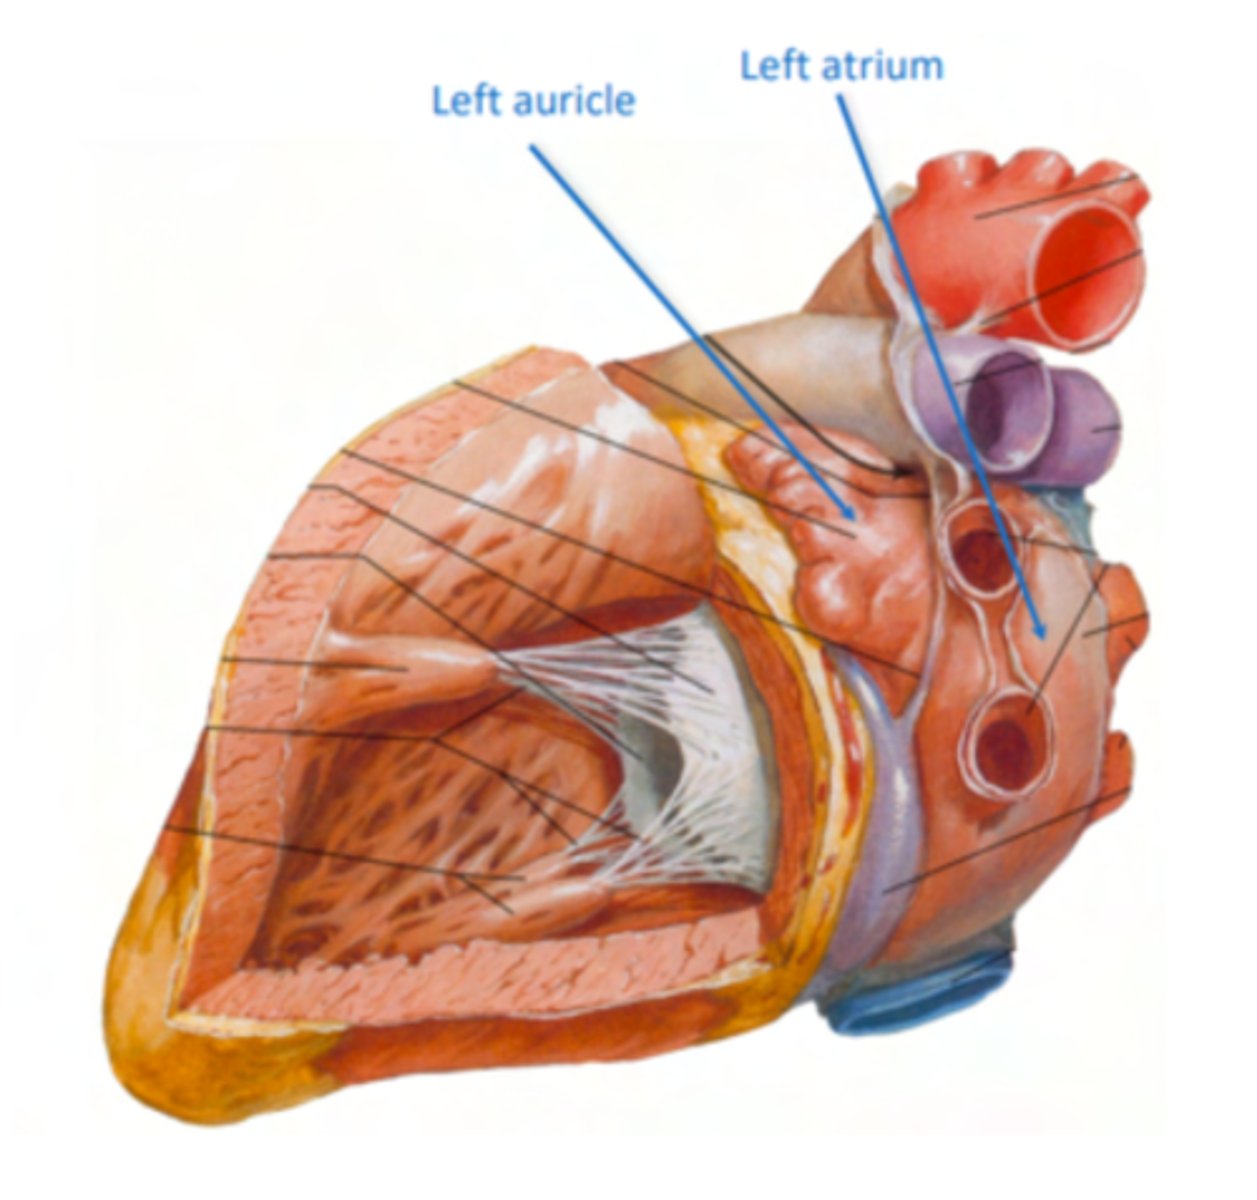

What are the atrial appendages?

Rough trabeculated region of the atria (Extensions of the atria)

External portions of the atria, (Real cavities of the right and left atrium being posterior to these auricles)

ALSO CALLED AURICLES

What are the two portions of the left atrium?

Smooth portion, originated from the incorporation of the

pulmonary veins. The proper atrium itself

Rough portion, the auricle or appendage,

SAME AS RIGHT ATRIUM